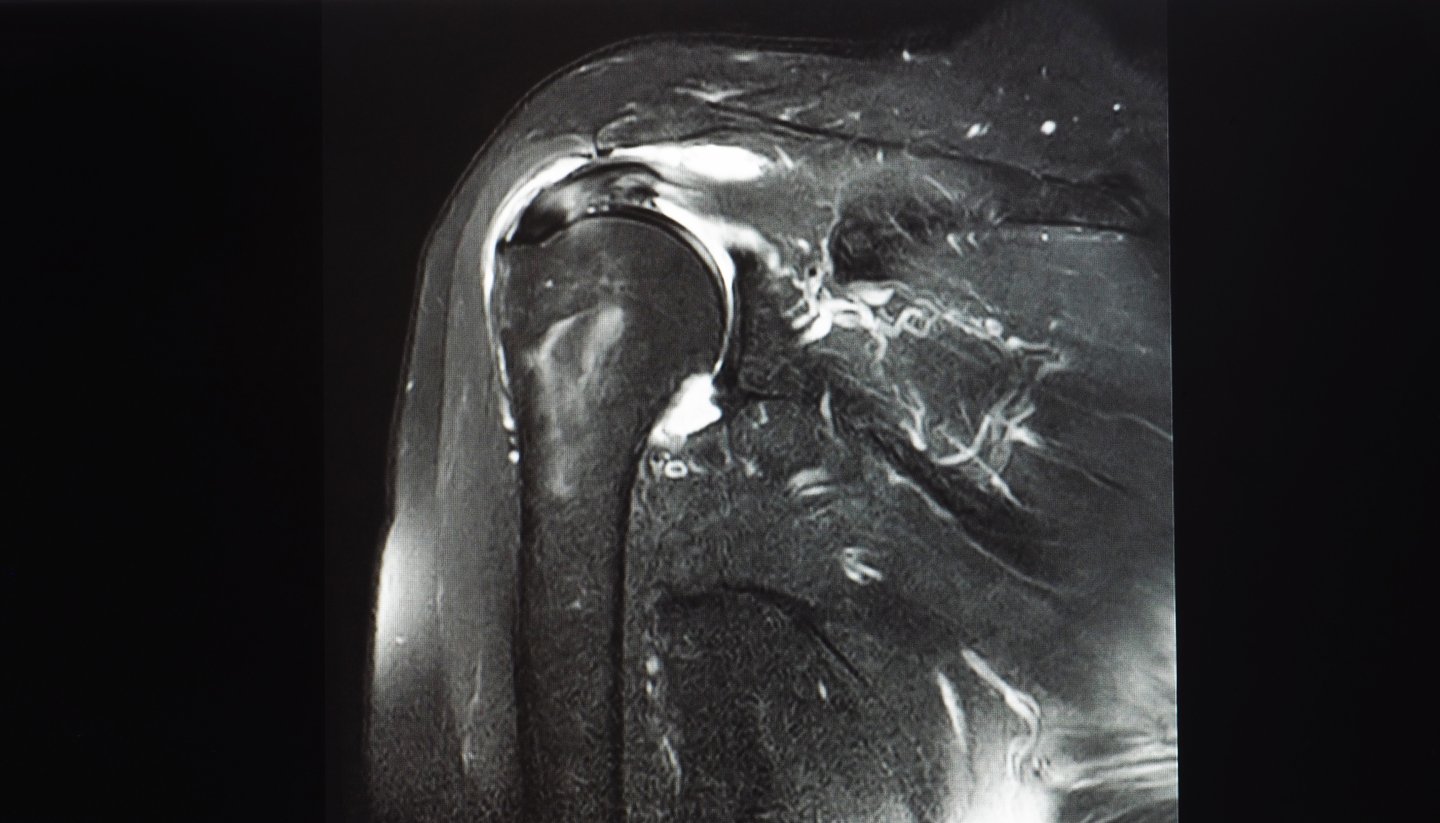

MRI machines are incredibly good at their job. They can detect minute structural changes in soft tissue. They can show a partial-thickness tear that's just a few millimeters. They can reveal tendon fiber disruption that might not affect function at all.

But exquisite sensitivity in detecting structural changes does not equal clinical relevance.

A structural change only matters if it changes how your shoulder functions or causes pain. And this study clearly shows that the vast majority of MRI-detected abnormalities do exactly neither.